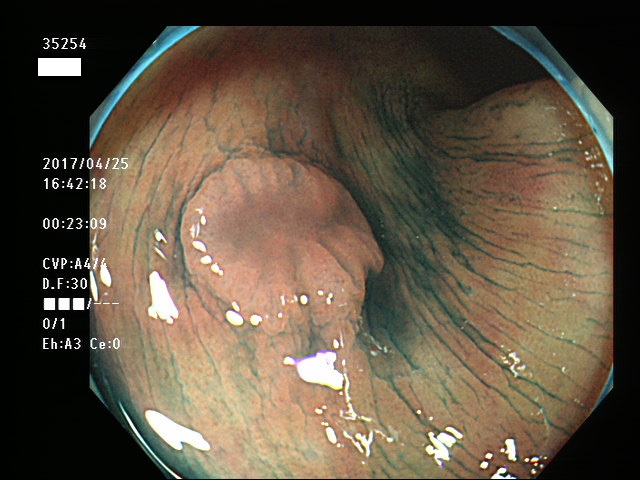

上記100名より抽出した平坦・陥凹型腺腫・SSAP(=癌化の危険が高いが見落としやすい病変)の内視鏡写真